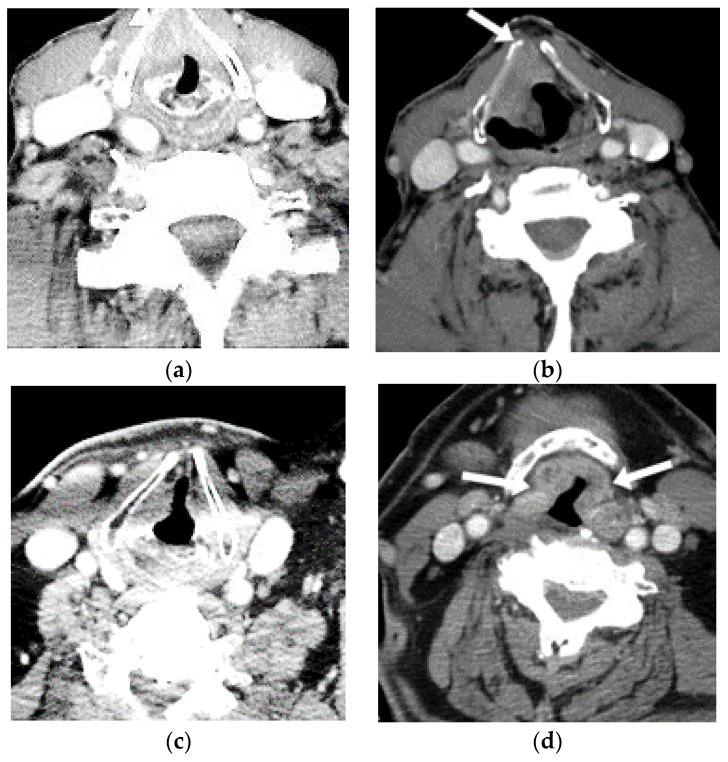

Recently, laryngeal cancer cases have increased drastically across the globe. Accurate treatment for laryngeal cancer is intricate, especially in the later stages. This type of cancer is an intricate malignancy inside the head and neck area of patients. In recent years, diverse diagnosis approaches and tools have been developed by researchers for helping clinical experts to identify laryngeal cancer effectively. However, these existing tools and approaches have diverse issues related to performance constraints such as lower accuracy in the identification of laryngeal cancer in the initial stage, more computational complexity, and large time consumption in patient screening. In this paper, the authors present a novel and enhanced deep-learning-based Mask R-CNN model for the identification of laryngeal cancer and its related symptoms by utilizing diverse image datasets and CT images in real time. Furthermore, our suggested model is capable of capturing and detecting minor malignancies of the larynx portion in a significant and faster manner in the real-time screening of patients, and it saves time for the clinicians, allowing for more patient screening every day. The outcome of the suggested model is enhanced and pragmatic and obtained an accuracy of 98.99%, precision of 98.99%, F1 score of 97.99%, and recall of 96.79% on the ImageNet dataset. Several studies have been performed in recent years on laryngeal cancer detection by using diverse approaches from researchers. For the future, there are vigorous opportunities for further research to investigate new approaches for laryngeal cancer detection by utilizing diverse and large dataset images.